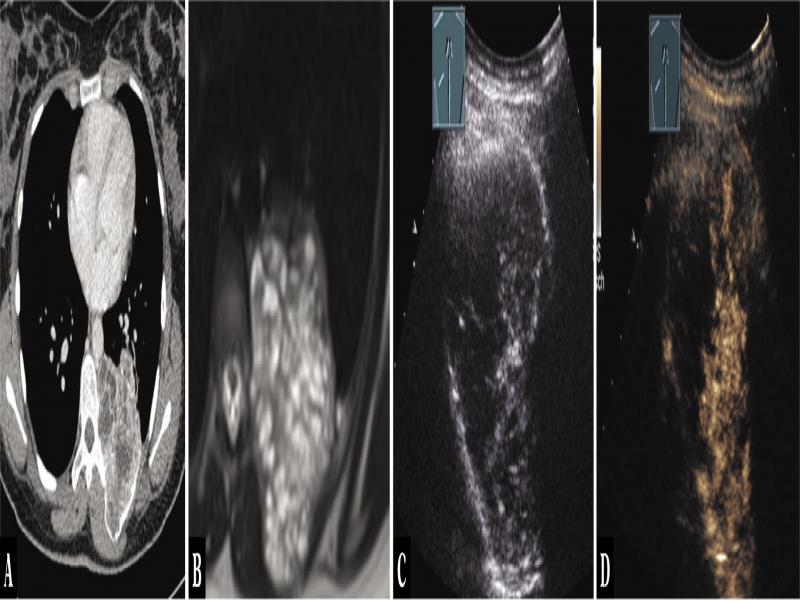

Fig. 19.

A 55-year-old female patient with thoracic pressure sensation and a mediastinal tumor in the posterior mediastinum, with an additional ventral pleural lesion on computed tomography (A). A history of malignant phyllodes tumors of the breast was known. Thoracic ultrasound indicated an inhomogeneous hypoechoic tumor (B), which on contrast-enhanced ultrasound showed a mixed central absent enhancement and marginal marked enhancement (C). Ultrasound-guided biopsy was performed, and the diagnosis of a metastasis from a malignant phyloid tumor of the breast was histologically confirmed